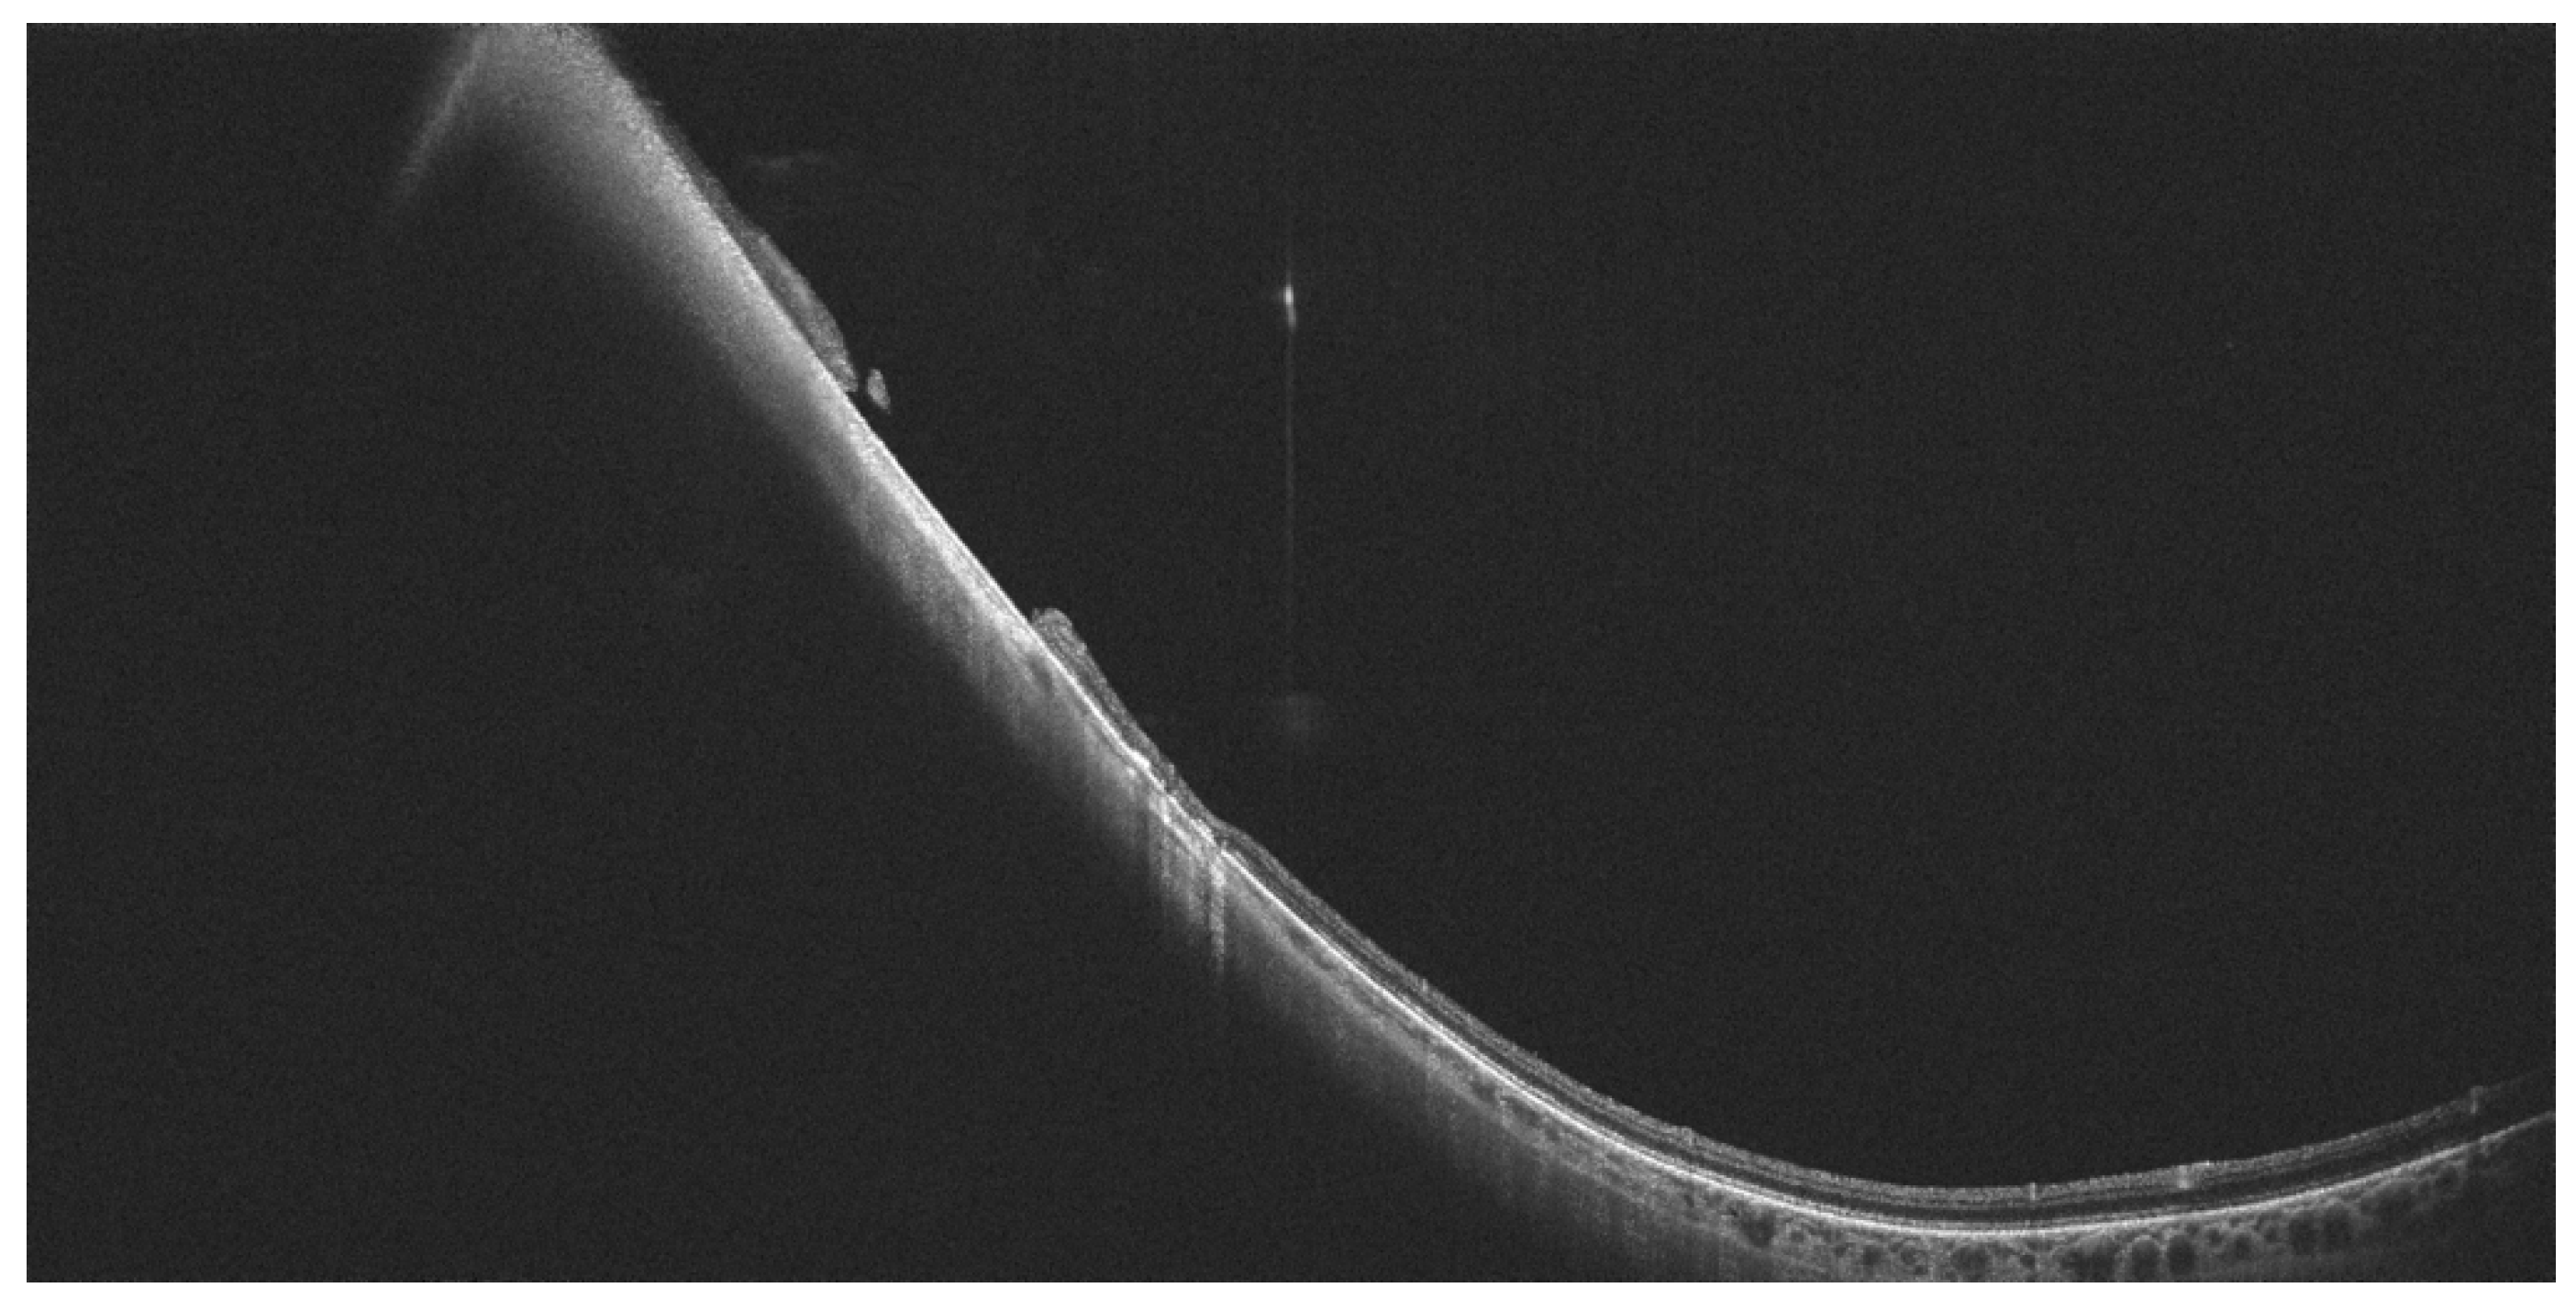

- Tsukahara, M.; Mori, K.; Gehlbach, P.L.; Mori, K. Posterior Vitreous Detachment as Observed by Wide-Angle OCT Imaging. Ophthalmology 2018, 125, 1372–1383. [Google Scholar] [CrossRef] [PubMed]